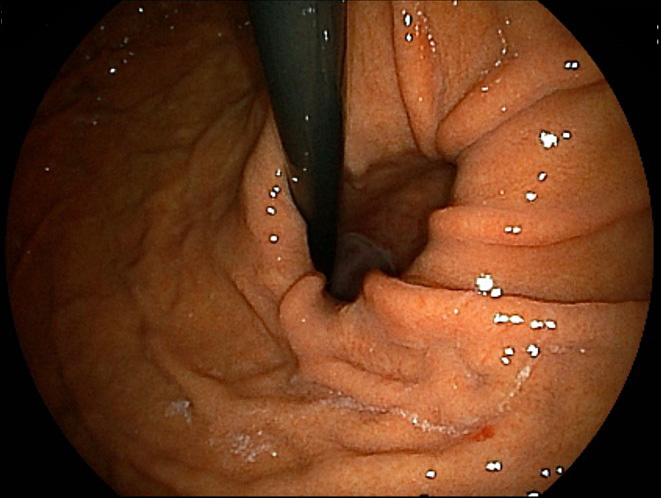

食道裂孔ヘルニア

胴体の内部は、胸部と腹部に分けられており、その境目に横隔膜があります。横隔膜には血管である大動脈と大静脈、そしてのどから腹部にある胃へ飲食物を運ぶ食道が通る裂孔があります。食道裂孔へルニアは、食道が通る裂孔に胃の一部がはみ出してしまっているもので、逆流性食道炎などの原因になります。

胴体の内部は、胸部と腹部に分けられており、その境目に横隔膜があります。横隔膜には血管である大動脈と大静脈、そしてのどから腹部にある胃へ飲食物を運ぶ食道が通る裂孔があります。食道裂孔へルニアは、食道が通る裂孔に胃の一部がはみ出してしまっているもので、逆流性食道炎などの原因になります。

発症原因は肥満や姿勢などによる腹圧の上昇、加齢による裂孔のゆがみやゆるみなどがあります。逆流性食道炎がある場合にはその治療を行いますが、症状が特になければ経過観察をしていきます。重い場合には手術を検討することもあります。